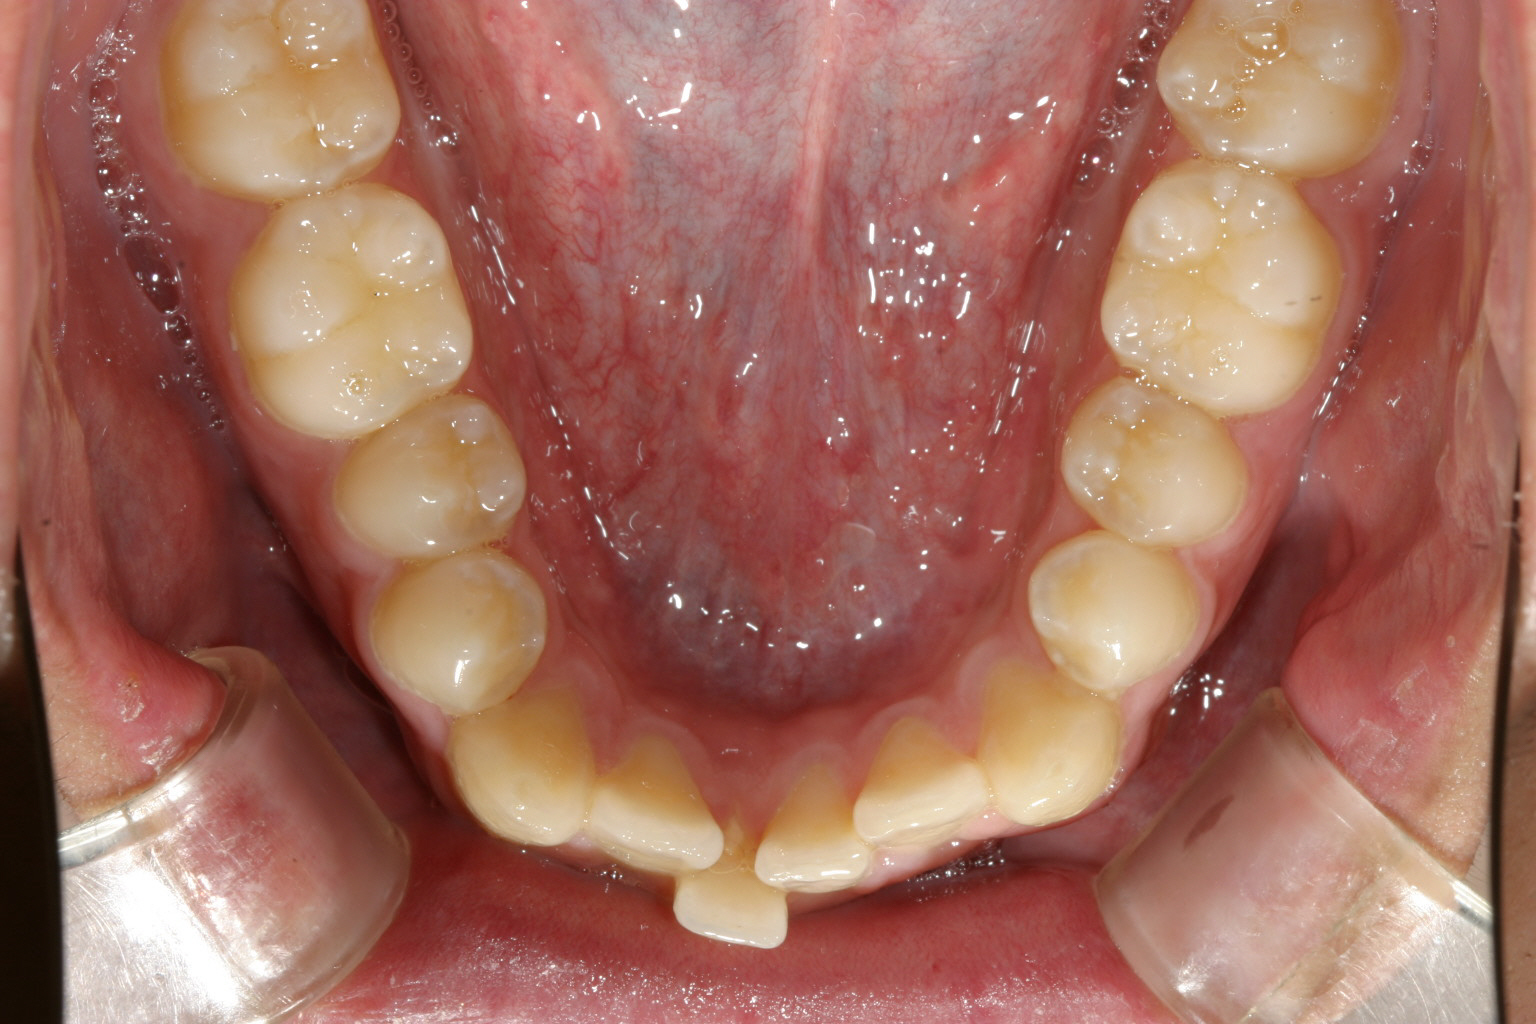

下顎もアーチが狭い為叢生になっています。

下顎も綺麗に改善しました。

奥歯のかみ合わせを緊密にするためこの様なアップダウンエラスティックを使用しました。 その際も元々少ししゃくれ気味だったためCLASSⅢエラスティックとしています。

最終的に咬み合わせが少し甘いと感じた時はこの様なアップダウンエラスティックを使用致します。こうする事によりかみ合わせが緊密になります。